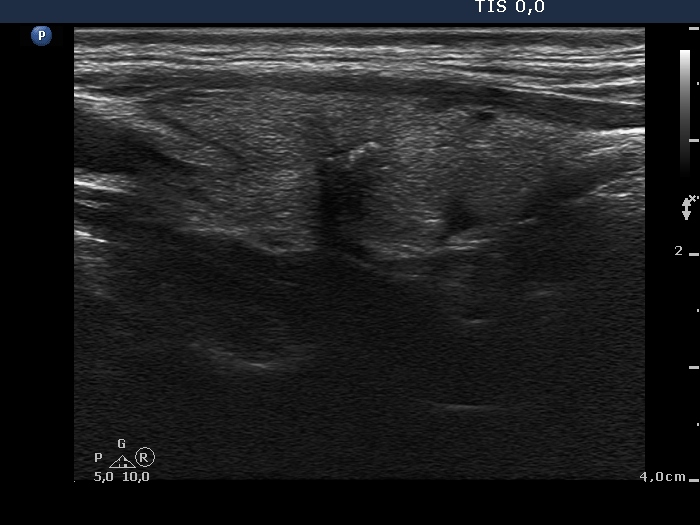

Right lobe, longitudinal scan

Right lobe, longitudinal view. The nodule contains microcalcifications and coarse calcifications, too.